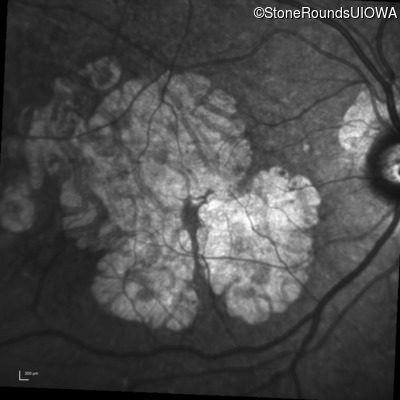

AR Stargardt Disease (IIA)

Age at visit: 59 years

This 59 year old man has noticed some blank spots near the center of his vision over the last 2 years.

Diagnosis & molecular findings

Disease Gene Allele 1 variant(s) Allele 2 variant(s) Inheritance mode

AR Stargardt Disease ABCA4 Leu2027Phe CTC>TTC IVS30+1321 A>G AR